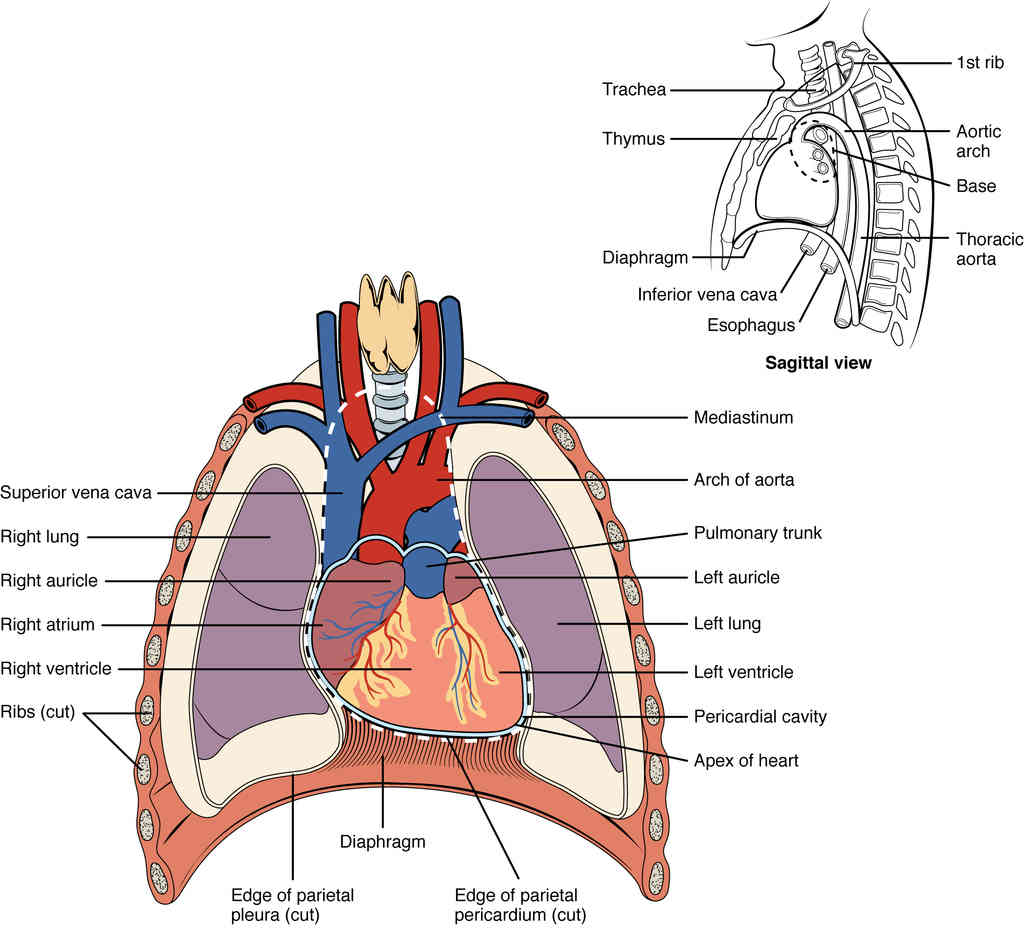

This page is under construction. For now, it is just a resource of the images found in the OpenStax Anatomy and Physiology Handbook. It wil slowly change into a revision tool. Each slide has a number. Use this to refer to the slide. When completed, it will have an unlabelled section, with labelled slides in parallel. On the unlabelled slides, write your answer and use the labelled slide to assess yourself. Keep track by also noting the number on each slide. Improvement at each attempt is important, more so than full marks on a first attempt.